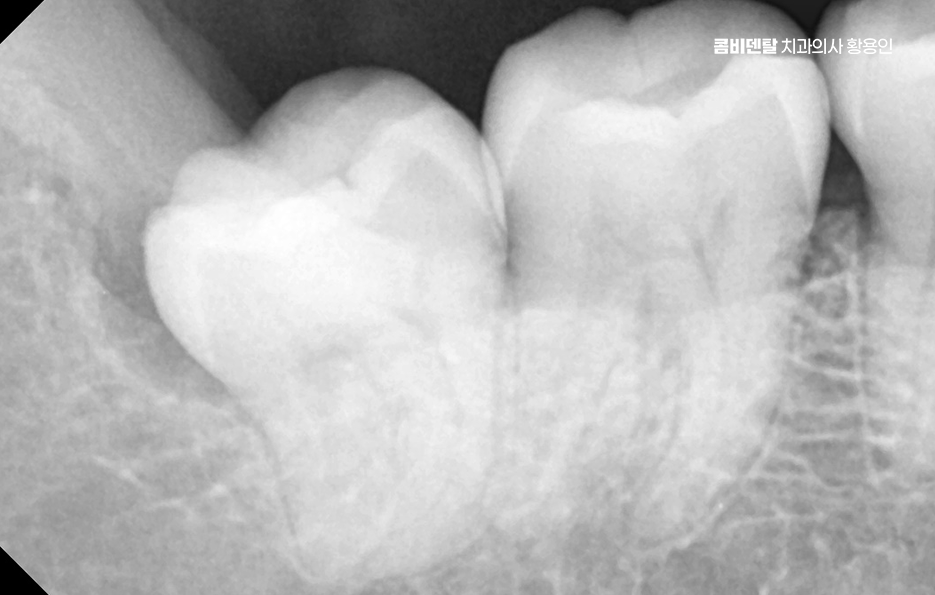

특히 아래쪽 사랑니는 공간이 부족한 경우가 많아서 정상적으로 나기보다는 매복되거나 비뚤게 나는 경우가 많아서 문제가 생기기 쉽고, 결국 문제가 심해지다가 발치를 안하기 어려운 단계로 이어지는 경우가 많이 있어요

아래 사랑니에서 문제가 생기는 대표적인 원인은 공간 부족으로 사랑니가 나올 무렵에는 앞선 치아들이 이미 자리 잡고 있기 때문에 사랑니가 나올 자리가 부족한 경우가 대부분이어서 사랑니가 잇몸 속에서 옆으로 누워서 자라거나, 부분적으로만 머리를 내밀고 자라는 일이 많다보니 이런 상태에서는 칫솔이 닿지 않아서 음식물이 끼기 쉽고, 세균이 쌓이면서 염증이 생기기 쉬운 거예요.

사랑니가 제대로 나지 않으면 그 앞에 있는 어금니에도 영향을 줄 수 있는데 사랑니가 비스듬히 눌러주는 방향으로 자라면 그 앞 치아 뿌리에 압박이 생기고, 치아 사이에 음식물이 자주 끼게 되면서 충치가 생기거나 잇몸 염증이 퍼지게 되는 것이며 앞 치아에 생긴 충치는 인접면 충치인 경우가 많기 때문에 일반 충치보다 더 치료가 어렵고, 경우에 따라서는 신경치료 까지 이어질 수도 있었어요.